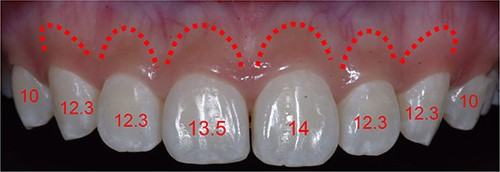

The length of the tooth crowns was clinically measured on the dental model (see Fig. 2), whereas the anatomical length was evaluated through CBCT images (see Figs 3 and 4). Based on the anatomical crown length, a smile design was created, and the patient was presented with a simulated smile before treatment (Figs 5 and 6). Upon approval of the simulated smile, a treatment plan was devised, establishing the future bone margin at 3-mm apical to the cementoenamel junction (CEJ) for each tooth, as indicated in Fig. 7.

In CBCT, determine the CEJ of each tooth to ascertain the anatomical crown length.

DSD with the anticipated gingival margin determined by the CEJ location.

Simulating the position of the proposed bone margin 3 mm apical to the anticipated gingival margin.